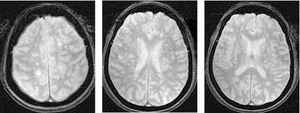

У режимі Т2*/T2 GRE на МРТ-зображенні головного мозку пацієнта з ГРЕМ візуалізуються двобічні гіперінтенсивні вогнища без геморагічного компоненту, що є типовою ознакою ГРЕМ, на відміну від гострого геморагічного лейкоенцефаліту (хвороби Херста) (рис. 3).

/images/nn257-1622023r3_.jpg)

На рисунку 4 наведено МРТ-зображення головного мозку пацієнта з гострим геморагічним лейкоенцефалітом (хворобою Херста) у режимі Т2*/T2 GRE, де візуалізуються двобічні гіперінтенсивні вогнища, два з яких містять геморагічний компонент, та в режимі Т2. А на рисунку 5 — МРТ-зображення головного мозку пацієнта з ГРЕМ у режимі Т2 — продемонстровано важливу ознаку ГРЕМ (на відміну від РС): відносну інтактність мозолистого тіла, стовбура мозку, середніх мозочкових ніжок та мозочка, які в разі РС, як правило, уражаються першочергово. Вказана ознака не завжди є показовою, але має високу інформативність для диференційної діагностики.

/images/nn257-1622023r4_.jpg)